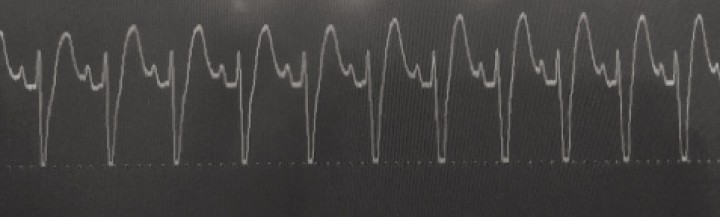

Las arritmias cardíacas, fundamentalmente son ventriculares, y se evidencian en aproximadamente el 40% de los perros con este síndrome. En concreto, la taquicardia ventricular es la arritmia que se presenta con mayor frecuencia (Fig. 4), aunque la fibrilación atrial y la taquicardia supraventricular también han sido descritas en estos pacientes.[ Monnet E. Gastric dilatation-volvulus syndrome in dogs. Vet Clin Small Anim Pract 2003; 33: 987-1005. [PubMed] , Cornell K. Gastric dilatation and volvulus. En Tobias KM, Johnston SA (ed): Veterinary Surgery Small Animal. Vol. 2. St. Louis, Missouri, Elsevier Saunders, 2012; 1508-1510. ]

<p>Imagen de un electrocardiograma en un paciente con DVG en el que se observa taquicardia ventricular caracterizada por una ausencia de ondas P (o, si se ven, no siempre preceden inmediatamente a un QRS) y anchos complejos QRS.</p>

Imagen de un electrocardiograma en un paciente con DVG en el que se observa taquicardia ventricular caracterizada por una ausencia de ondas P (o, si se ven, no siempre preceden inmediatamente a un QRS) y anchos complejos QRS.